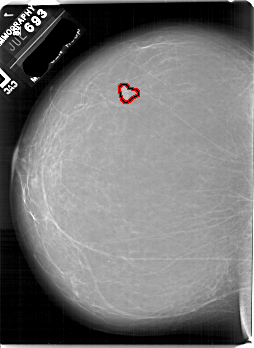

FILE: A_1882_1.LEFT_MLO.OVERLAY

TOTAL_ABNORMALITIES 1

ABNORMALITY 1

LESION_TYPE MASS SHAPE LOBULATED MARGINS CIRCUMSCRIBED

ASSESSMENT 3

SUBTLETY 5

PATHOLOGY BENIGN

TOTAL_OUTLINES 1

BOUNDARY